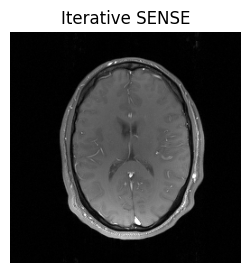

show_images(idat_us_sense.rss().squeeze(), titles=['Iterative SENSE'])

../_images/d87cf48f37004d16f1b3fec2b042602563d6bc8078bef297bf2cb8de0d84d488.png

This looks better! More information about the iterative SENSE reconstruction and its implementation in MRtwo can be found in the examples Iterative SENSE reconstruction of 2D golden angle radial data and Regularized iterative SENSE reconstruction of 2D golden angle radial data.